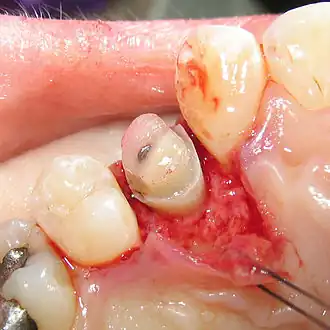

Verschiebelappen

Durch das Verfahren des apikalen Verschiebelappens – mit oder ohne Knochenresektion – wird ein Teil der Gingiva apikalwärts verschoben und dadurch der sichtbare Kronenanteil vergrößert.

Knochenresektion

Ohne Knochenabbau wird die Gingiva am betreffenden Zahn vorsichtig abpräpariert und der freigelegte Alveolarknochen mit einer Fräse (Rosenbohrer) im benötigten Umfang abgetragen. Um die Wurzeln der Nachbarzähne nicht zu beschädigen, wird dort der Knochen mit Handinstrumenten abgetragen. Der freigelegte Wurzelanteil wird einem Scaling unterzogen, um Reste des Desmodonts zu entfernen, damit ein Reattachment (Wiederanwachsen) vermieden wird.[9] Die Gingivawunde wird mit einer atraumatischen Naht versorgt.